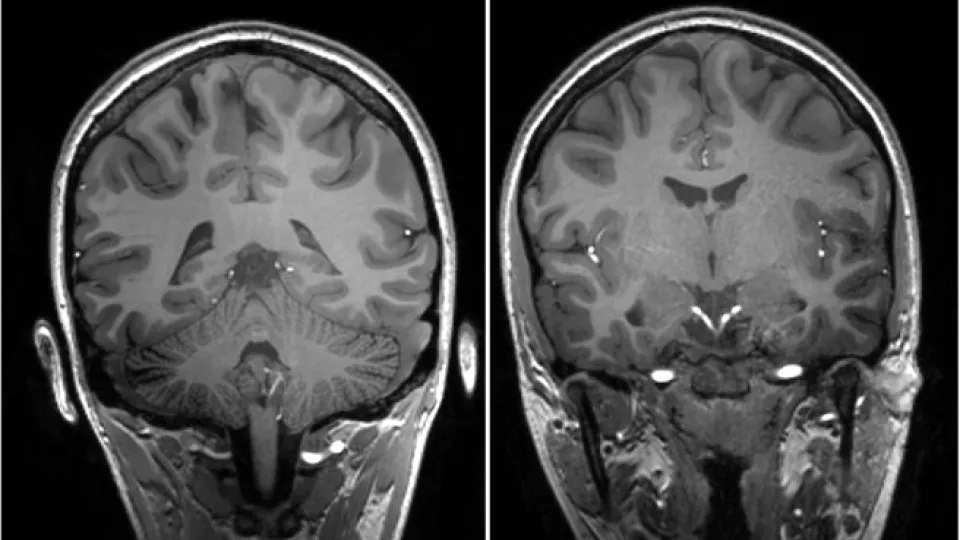

Our group focus on acquired brain injuries, such as traumatic brain injury (TBI), stroke, multiple sclerosis (MS), hydrocephalus, and their relation to neurodegeneration. We are interested in adaptive plasticity processes found in Alzheimer’s disease, Parkinson’s disease, and other neurodegenerative diseases.

We want to increase the understanding of neurodegenerative processes and cognitive decline related to acquired brain injuries through collaboration and knowledge exchange. Another aim we have is to understand adaptive and maladaptive plasticity in acquired brain diseases that compensate for neurodegeneration and to use refined imaging techniques to monitor stages of neurodegeneration from the molecular to the organ level.